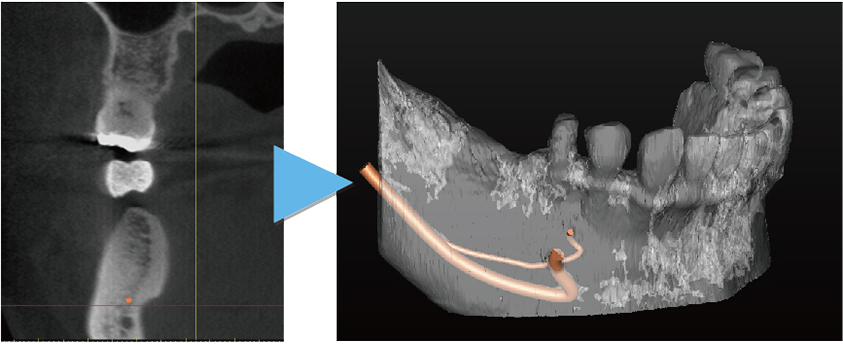

当院では安心安全なインプラント治療をより確実に行うために、すべてのインプラント治療で3Dコンピューターシミュレーションシステム「シンプラント プロ」で歯科CT画像からデータ解析を行い、サージガイドを作成するコンピューターガイデッド インプラント治療を行っています。

シンプラント プロのコンピューターガイデッド インプラント治療では、歯科CT画像から3D画像を構築し、骨の厚みや神経の走行などを視覚的に診査できます。

そして嚙み合わせ、骨の厚みや神経の走行からからみて三次元的に理想的なインプラントの位置を画像上でシミュレーションすることができます。これにより手術を行う前に安全で理想的なインプラントの位置を決定することが可能になりました。

歯科CTデータからシンプラントで3D画像を表示して骨の厚みや神経、血管の走行を検査します

噛み合わせ、骨の厚みや神経の走行からみて理想的なインプラントの位置を決定

インプラント治療の仕上がりのイメージは画像で患者様も視覚的に確認できます